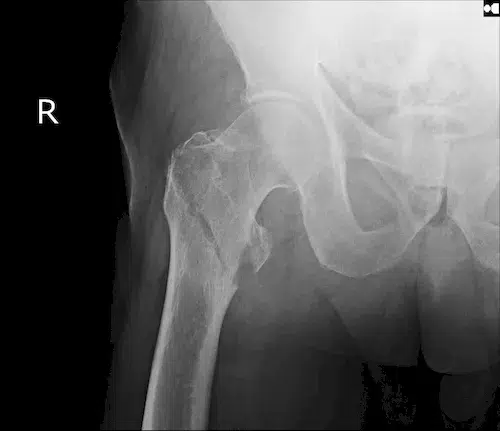

| ▸ | Röntgen Erkennung von Knochenbrüchen (zuverlässige Ergebnisse erst im späteren Krankheitsverlauf – neue, starke Rückenschmerzen; chronische Rückenschmerzen unbekannter Ursache; hohes Lebensalter; niedrige Knochendichte; mehrere, alte Brüche; Größenverlust von > 5 cm seit 25. Lebensjahr und > 2 cm bei Kontrolluntersuchungen) |

Röntgenaufnahmen von verschiedenen Knochenbrüchen bei Osteoporose

Diese Diagnostikmethoden kombiniert sind von großer Bedeutung, um individuelle Risikoprofile zu erstellen und eine präzise Behandlung einzuleiten. Eine frühzeitige Untersuchung ermöglicht es Ihnen, gezielt Maßnahmen zu ergreifen und so die Stabilität Ihres Knochengerüsts langfristig zu sichern.